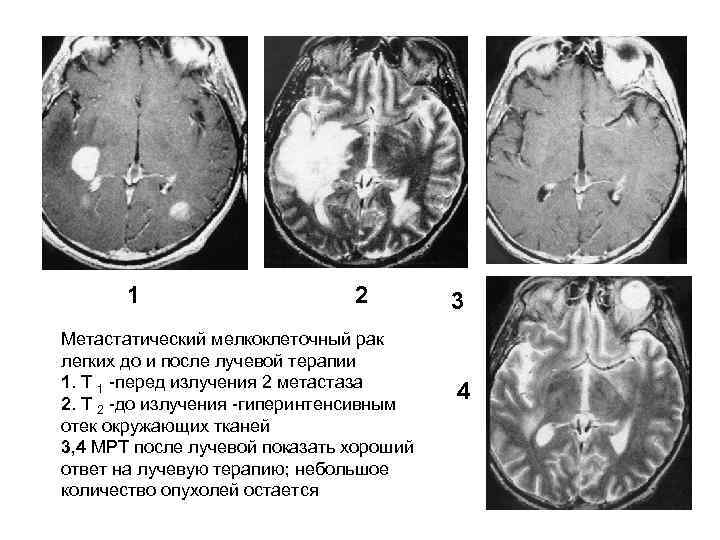

1 2 3 Метастатический мелкоклеточный рак легких до и после лучевой терапии 1. T 1 перед излучения 2 метастаза 2. Т 2 до излучения гиперинтенсивным 4 отек окружающих тканей 3, 4 МРТ после лучевой показать хороший ответ на лучевую терапию; небольшое количество опухолей остается 59